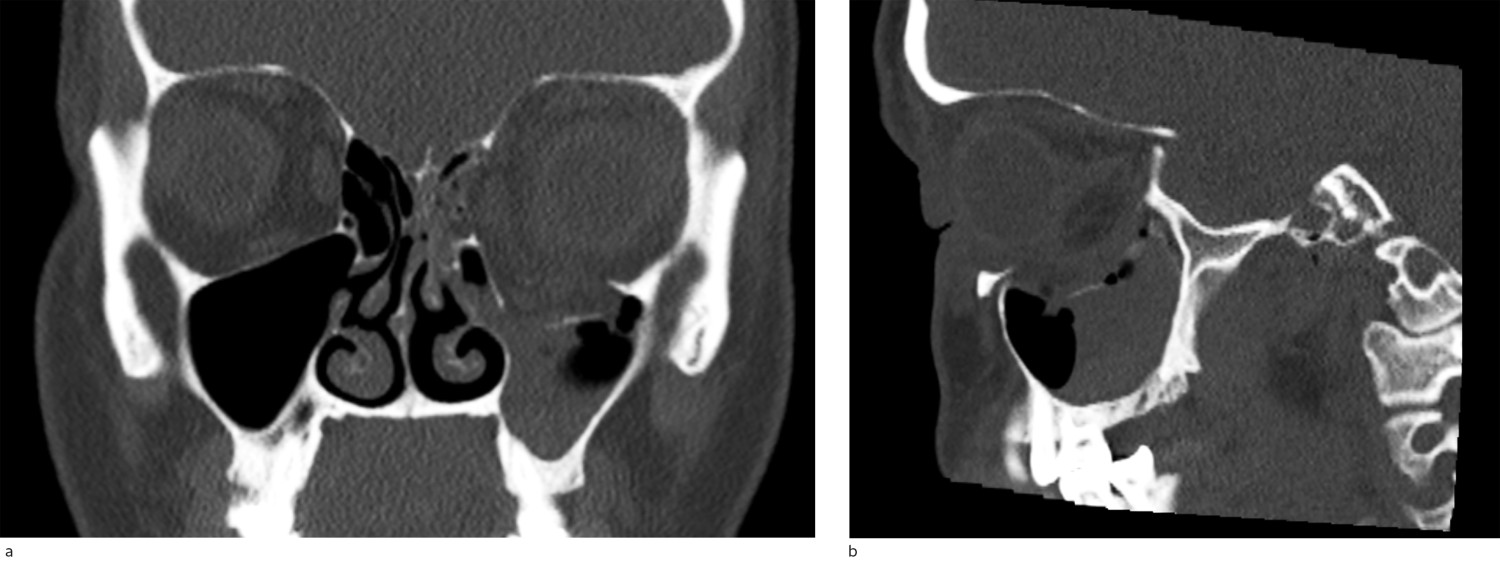

CT is the preferred diagnostic imaging technique for the detection of orbital fractures. If a fracture is suspected, a facial bone CT scan with thin slices (1 mm) should be ordered. This can reveal the fracture's location, size and any involvement of extraocular muscles (Figures 3a and 3b). In addition, any potentially pressure-causing haematoma related to the fracture can be identified. The position of the globe and whether there is proptosis (exophthalmos, bulging eye) can also be evaluated on the axial slices. In some cases, clinical assessment of this can be difficult if there is considerable periorbital swelling.